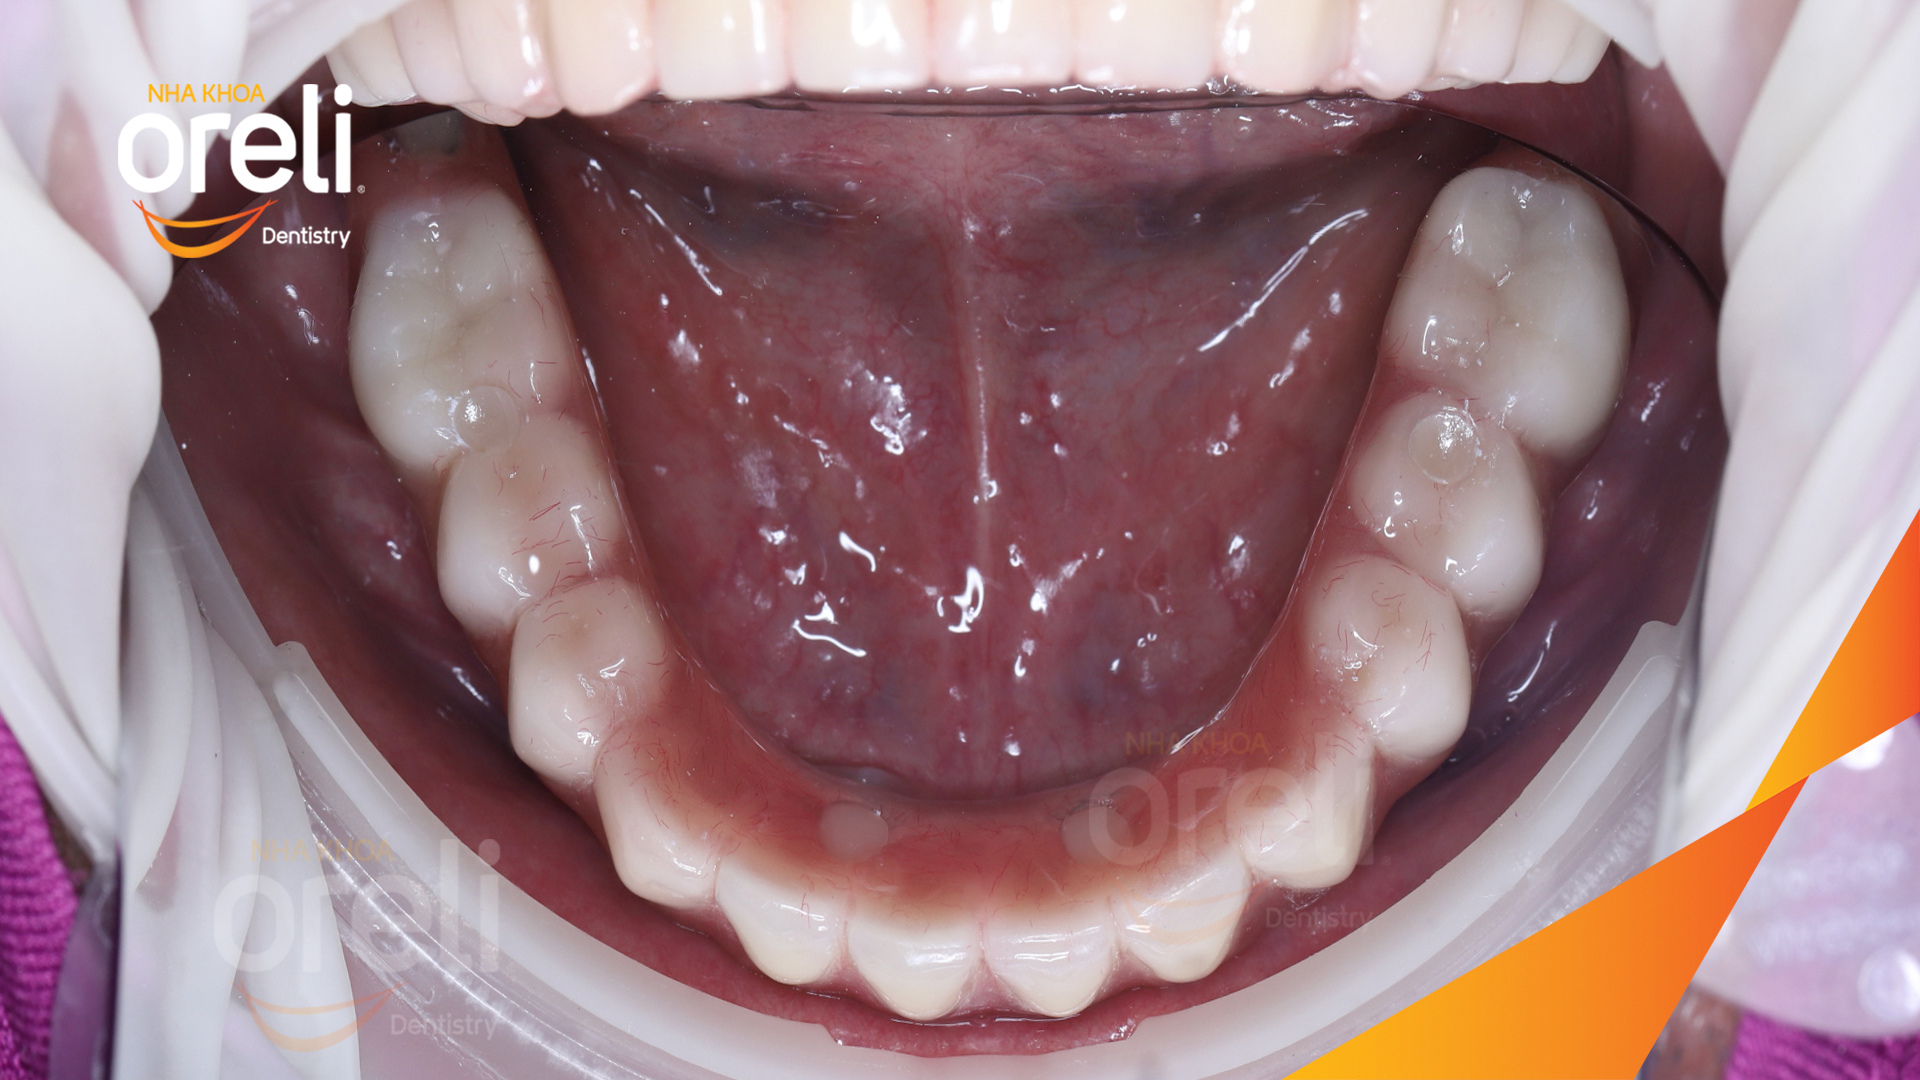

Ca trồng răng implant toàn hàm phục hồi ăn nhai và thẩm mỹ nụ cười. Kết quả thực tế trước và sau điều trị tại Nha khoa Oreli.

Tình trạng: Mất răng toàn bộ hàm trên và hàm dưới

Giải pháp: Trồng răng implant hai hàm với phục hình tạm

Kết quả: Ăn nhai trở lại và nụ cười thẩm mỹ

Hình ảnh thực tế